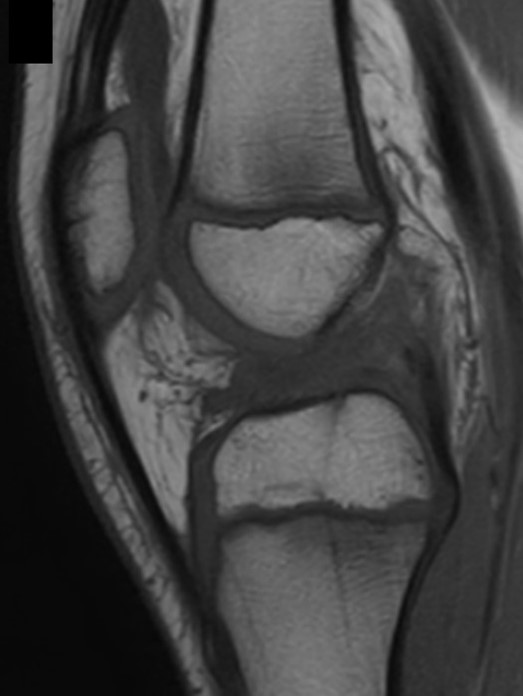

Figura 1: Lesione di LCA in paziente di 7 anni con immaturità scheletrica